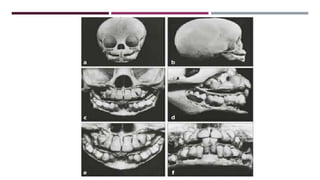

• #13 During the prenatal teeth and also some time after birth, anterior tooth are rotated or overlapping

• #15 Overview of dentition and jaws from 3 years Jaws are still small at birth In the anterior regions , tooth buds are rotated and overlap each other From birth to 6 months, jaws grow considerably in transvers direction to accommodate the incisors

• #16 e) Mandibular symphysis ossifies prior to eruption of mandibular central deciduous incisors (no more transverse growth for mandible) f) Both jaws continue to grow posteriorly resulting in space for distal migration of developing deciduous molars g) First deciduous molars emerge and occlusion is established h) Jaws grows more posteriorly to accommodate the deciduous 2nd molars which emerge after 1 year and subsequently 1st permanent molars

• #17 Skull at 8 months of age b) Mandibular border narrow c) Developing dentition completely fills the space between eye sockets and nasal floor superiorly and mandibular base inferiorly d) Occlusal plane of the not yet erupted deciduous molars is a concave plane e) Incisal edges of maxillary incisors are at same level with only centrals emerged f) Root formation of lateral incisors lags behind that of central incisors

• #18 Skull at 6 years of age All deciduous teeth have erupted. Nasal floors is situated inferiorly to the lower margin of eye sockets. Deciduous teeth are in upright position perpendicular to the occlusal planes Space between nasal floor and mandibular base is completely filled with teeth Space available for permanent canines and premolars is more limited in maxilla than in mandible